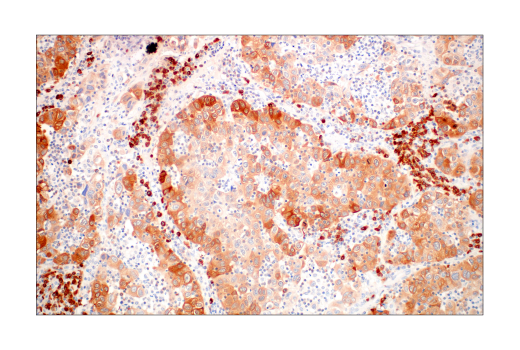

W, IHC-Bond, IHC-P, FC-FP

W: Western Blotting IHC-Bond: IHC Leica Bond IHC-P: Immunohistochemistry (Paraffin) FC-FP: Flow Cytometry (Fixed/Permeabilized)